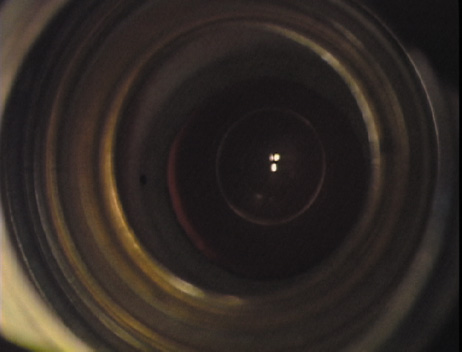

Case 3 is a 48-year-old bilateral hyperope who presented for a refractive surgical consultation. The refraction in his left eye was found to be +3.25 +1.75 × 85. Keratometry was somewhat flat but confirmed WTR cylinder as did corneal topography. Based upon the patient's age, refraction, and somewhat shallow anterior chambers, the decision was made to proceed with a refractive lens exchange. The NAPA nomogram called for LRIs of 55 to 60 degrees with intraoperative pachymetry. Intraoperative keratoscopy confirmed the steep 85-degree meridian (Figs. 2029).

Fig. 20. Keratoscopy, after lifting of the speculum to relieve induced pressure and distortion of the corneal mires, confirms the steep axis of 85 degrees.